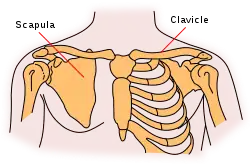

A scapular fracture is a fracture of the scapula, the shoulder blade. The scapula is sturdy and located in a protected place, so it rarely breaks. When it does, it is an indication that the individual was subjected to a considerable amount of force and that severe chest trauma may be present.[1] High-speed vehicle accidents are the most common cause. This could be anywhere from a car accident, motorcycle crash, or high speed bicycle crash but falls and blows to the area can also be responsible for the injury. Signs and symptoms are similar to those of other fractures: they include pain, tenderness, and reduced motion of the affected area although symptoms can take a couple of days to appear. Imaging techniques such as X-ray are used to diagnose scapular fracture, but the injury may not be noticed in part because it is so frequently accompanied by other, severe injuries that demand attention. The injuries that usually accompany scapular fracture generally have the greatest impact on the patient's outcome. However, the injury can also occur by itself; when it does, it does not present a significant threat to life. Treatment involves pain control and immobilizing the affected area, and, later, physical therapy.

The scapula is protected from the front by the ribcage and chest, and from the back it is protected by a thick layer of muscles.[3] Also, the scapula is able to move, so traumatic forces exerted on it are dissipated, not absorbed by the bone.[3] Thus a large amount of force is required to fracture it.[4]